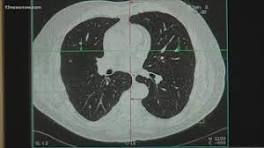

| Lung Cancer Tumor Sizes, according to the National Library of Medicine #greenscreen ... - Instagram My name is Aurora Lucas. I am a three year lung cancer survivor and a question that I've been asked is how big were the lung cancer tumors when they ...